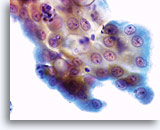

Postpartum

High power view of parabasal cells during postpartum. Note presence of glycogen and low N/C ratio. 60X